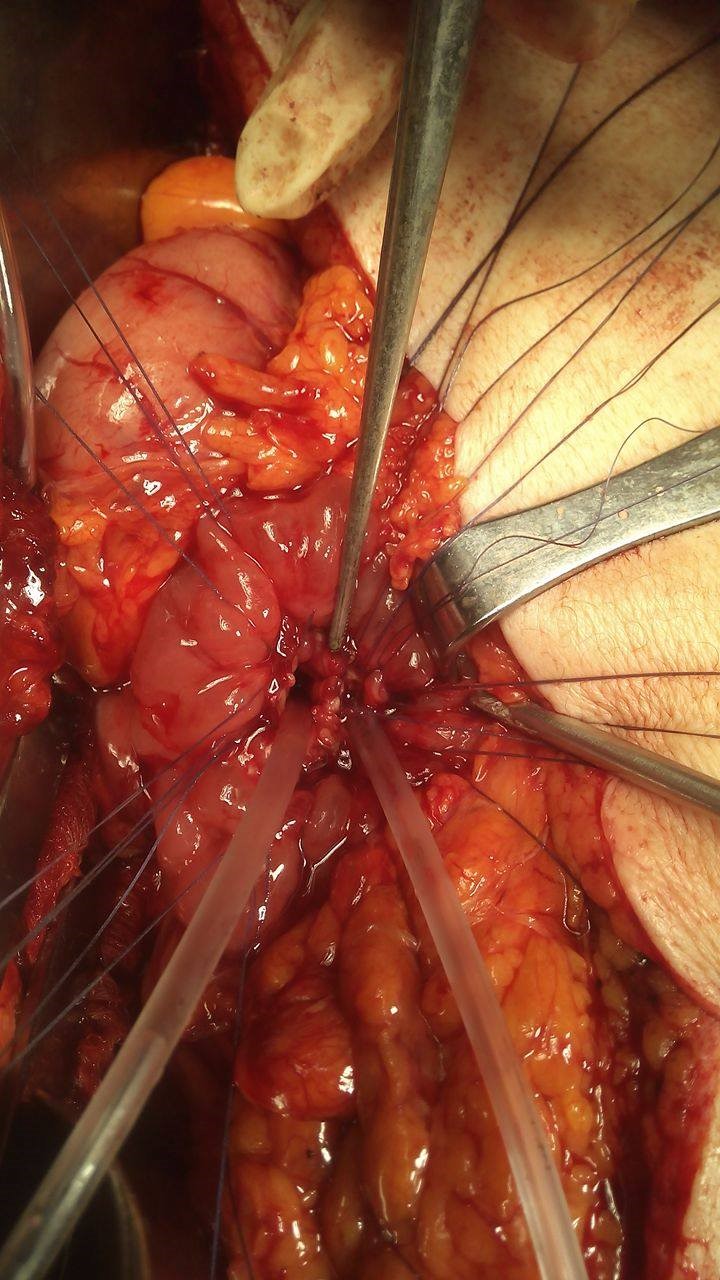

Completion of the pancreaticogastric anastomosis – Green arrow – demonstrates the pancreas secured within the gastric lumen (Courtesy Dr. V. Penopoulos)